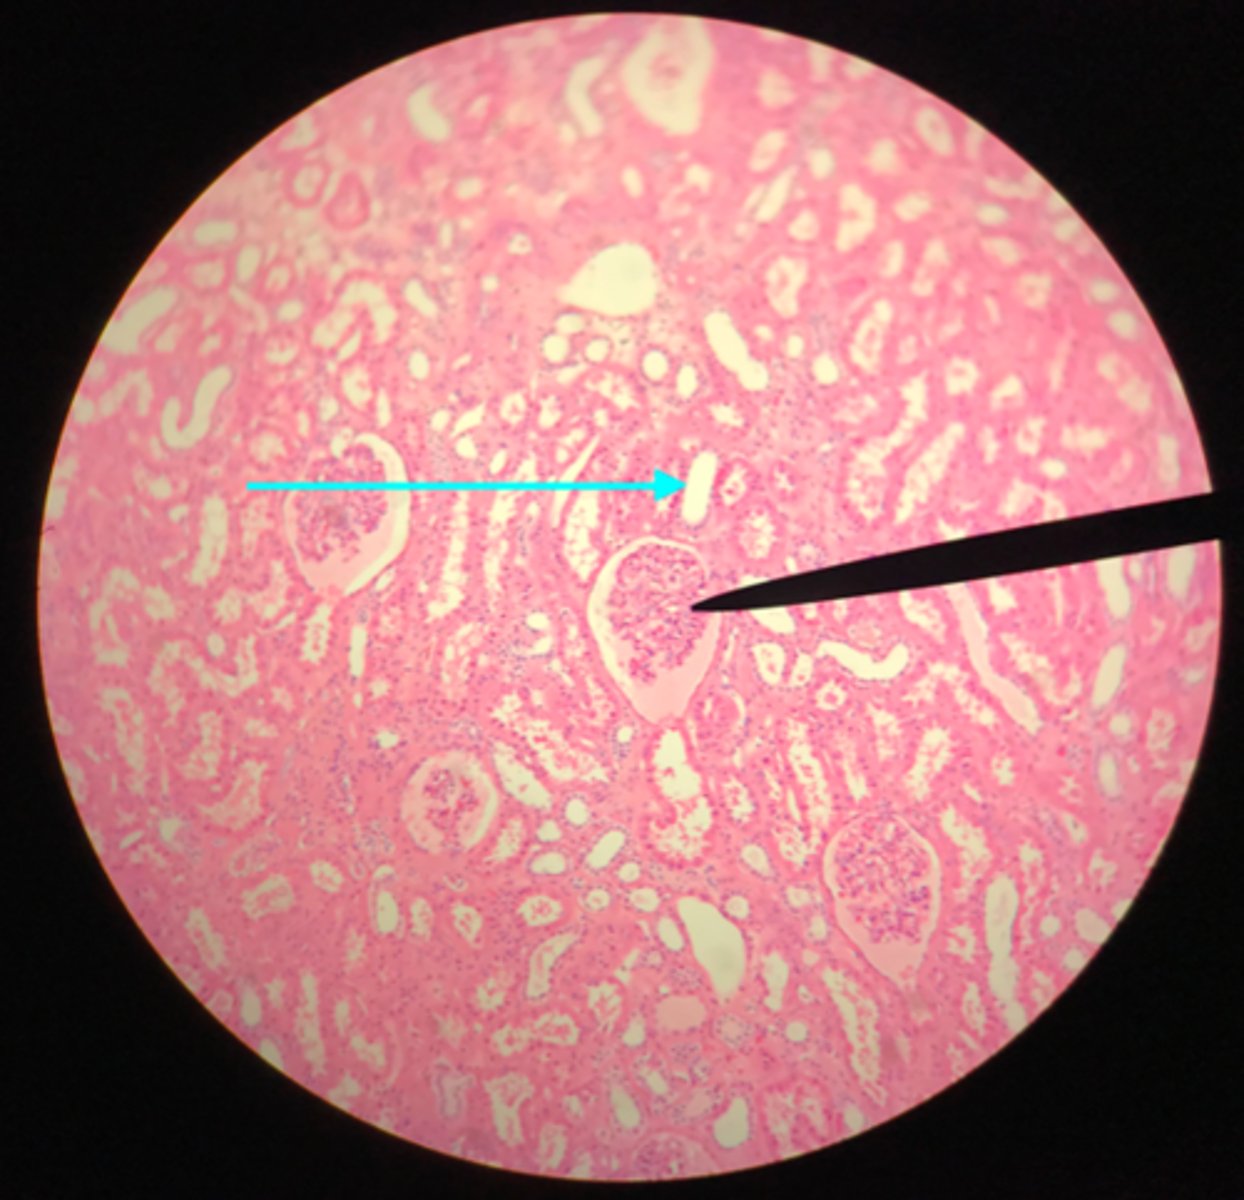

Cortex of the kidney

There are glomerular corpuscles present in the cortex. They are not present in the medulla

What layer of tissue of which organ is depicted on this slide? How can you tell?

Glomerular (Bowman's) capsule (in the cortex)

What structure of the kidney is the blue arrow pointing at?

Glomerulus

What structure of the kidney is the pointer placed on?

Renal tubules (in the cortex)

What structure of the kidney is the blue arrow pointing at?